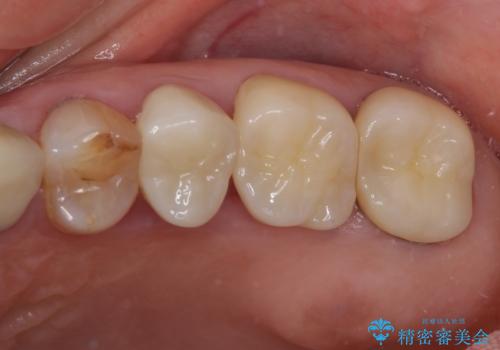

全ての奥歯の銀歯をセラミックに メタルフリー治療

途中体調を崩されてしまい、その間に仮歯が外れてしまうなど、治療期間が長引いてしまいました。

治療期間はかかってしまいましたが、念願のメタルフリーとなり、患者様には大変満足していただきました。